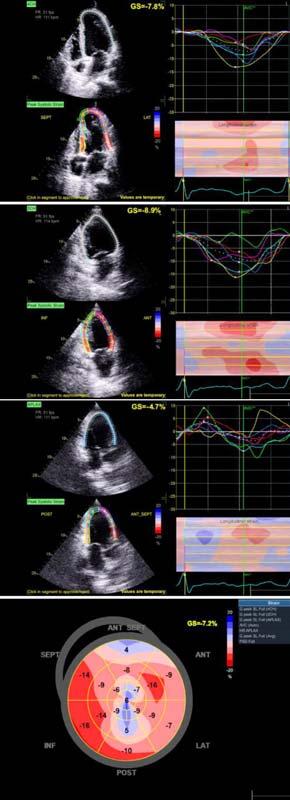

Aims and Objectives : To observe change in Left Ventricle (LV) function as assessed by Global Longitudinal Strain (GLS) at 3 months and at 6 months in cohort of STEMI patients undergoing extended Pharmaco-invasive therapy.

Results : Mean age of the sample population was 60.18±8.289 years. All of the patients were thrombolysed within a mean window period of 7.57±2.744 hours. The mean time to revascularization was 69.35±22.97 hours after thrombolysis. The mean GLS were -11.5±3.3, -13.2±4.9 and -15.1±3.1 at pre-procedure, at 3 months follow-up and at 6 months follow-up respectively. When change in mean GLS at 6 months from baseline was compared with respect to the time to PCI, mean change in GLS at 6 months was found to have strong linear correlation with time to PCI after thrombolysis (r=0.773, p24 hours) still outcomes are better in those in whom PCI was done early ie, within 48 hours (by -4.50) than those in whom PCI was done after 96 hours (by -2.63) of Thrombolysis.

Conclusion : Extended Pharmaco-invasive strategy is a reasonable option if PCI cannot be performed within the first 24 hours. This strategy is thus likely to widen the window between Thrombolysis and PCI. There is a significant improvement of LV function as assessed by GLS at short-term follow-up of 6 months.

To assess the LV function in such patients we would utilize various echocardiographic parameters such as Ejection Fraction by Simpson’s biplane method, end diastolic volume, end systolic volume, stroke volume and Global longitudinal strain through Speckle

tracking2. Strain is a sensitive tool that correlates well with other measures of cardiac function, and detect changes in myocardial contractility, both normal and abnormal, across a wide range of ischemic syndromes3.

All patients underwent 2D-TTE before coronary angiogram and PCI. The LV ejection fraction was assessed by Simpson’s biplane method, and GLS was estimated by speckle-tracking echocardiography. The following Echocardiographic parameters were also analysed: End Diastolic Volume, End Systolic Volume, Stroke Volume, Mitral Regurgitation.

The mean LV ejection fraction were 46.54±8.8%, 47.9±8.6% and 51.12±7.6% at preprocedural, at 3 months follow-up and at 6 months follow-up respectively. The mean increase in Left Ventricular Ejection Fraction (LVEF) was 1.3% at 3 months follow up and 4.6% at 6 months follow-up. The mean Global Longitudinal Strain (GLS) were -11.5±3.3, -13.2±4.9 and -15.1±3.1 at preprocedural, at 3 months follow-up and at 6 months follow-up respectively. The mean increase in GLS was -1.66 at 3 months follow up and -3.6 at 6 months follow-up from baseline.

When the mean change in GLS at 3 months and at 6 months follow up from baseline was correlated with respect to the number of risk factors present, a significant moderate linear correlation (r=0.513 at 6 months, p<0.01) was found inferring better improvement in GLS in patients with no risk factors or 1 risk factor (by -2.91, -2.64 at 3 months and -4.92, -4.28 at 6 months) than those with all 2 or 3 risk factors (by -1.78, -0.69 at 3 months and -2.85, -1.53 at 6 months).

When change in mean GLS at 6 months with that at baseline was compared with respect to the time to intervention (PCI), mean change in GLS at 6 months was found to have strong linear correlation with time to PCI after thrombolysis (r=0.773, p<0.01) inferring that though delayed (>24 hours.) still outcomes are better in those in whom PCI was done early ie, within 48 hours. (by -4.50) than those in whom PCI was done after 96 hours (by -2.63) of thrombolysis. There was no significant difference noted at 3 months follow up in GLS.

When correlated with time to intervention after PCI this study also clearly shows that the improvement in post-PCI LV function, as assessed through GLS, are better in those in whom PCI was done early (ie, <48 hours in this study) than in those whom PCI is still delayed (ie, >96 hours). Such a change could not be detected through LVEF. Thus, the assessment of LV function after PCI in patients with STEMI was superior with GLS when compared to 2D LVEF. As strain imaging is an inexpensive tool, it can be applied easily to assess LV function in the large subset of population (Figs 1A, 1B & 2).